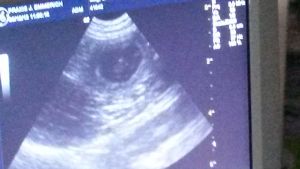

Röntgentermin beim Tierarztteam Jörn Emmerich in Vallendar 08. Januar 2014 Also ... gestern war es soweit und wir haben ein gaaaanz spezielles Bild von Keks geschossen. Zuerst war ich zwar etwas irritiert, dass das Bild mit Keks allein (ohne mich) gemacht wurde, aber der Maus ging es die ganze Zeit sehr gut und sie war auch ganz brav!!! Nach dem Bild durfte ich zur Besprechung rein. Herr Emmerich ist von Keks´ körperlichem und gesundheitlichen Zustand begeistert und er sieht keinerlei Probleme auf uns zukommen. Nichts desto trotz stehen er und Frau Dr. Häberlein nun auf Abruf bereit. ![]() Wer nun möchte, kann ja mal versuchen, die kleinen Kekskrümelchen zu zählen. Ich gebe einen Tipp: Es sind mehr als 6, aber weniger als 10. :-) Bisher ist Keks noch total entspannt, auch wenn wir am Samstag einen Fehlalarm hatten (Ihre Temperatur war schon auf 37,3 Grad). Nun wird fleißig jeden Tag Fieber gemessen und ein Protokoll geführt. Seit 2 Tagen schläft Keks in der "Keksdose" (davor in meinem Bett) und ich seit Samstag davor. Sie ist noch sehr ruhig, anhänglich und hat einen Bauch mit Beulenbildung :-) Die kleinen Kekskrümelchen kann sogar jetzt jeder sehen, der einfach Keks´Bäuchlein mal länger anschaut. Ich sage immer: Die Handballmannschaft übt das prellen :-) Da kommen auch die Gefühle der eigenen Schwangerschaft wieder hoch, wenn wir so zusammen liegen und die kleinen Krümelchen in meiner Hand sich drehen und wenden oder schon das Laufen üben ... einfach unbeschreiblich! Morgen kommen Babs, Rolf und Mini. Gästezimmer ist vorbereitet (seit Samstag :-)) und dann kann es bei Keks losgehen. Sobald wir Bilder und Info´s über die kleinen Kekskrümelchen haben, dann könnt Ihr das hier nachlesen - schneller über Facebook (wird öffentllich sein). Bis dahin bitte DAUMEN drücken! |